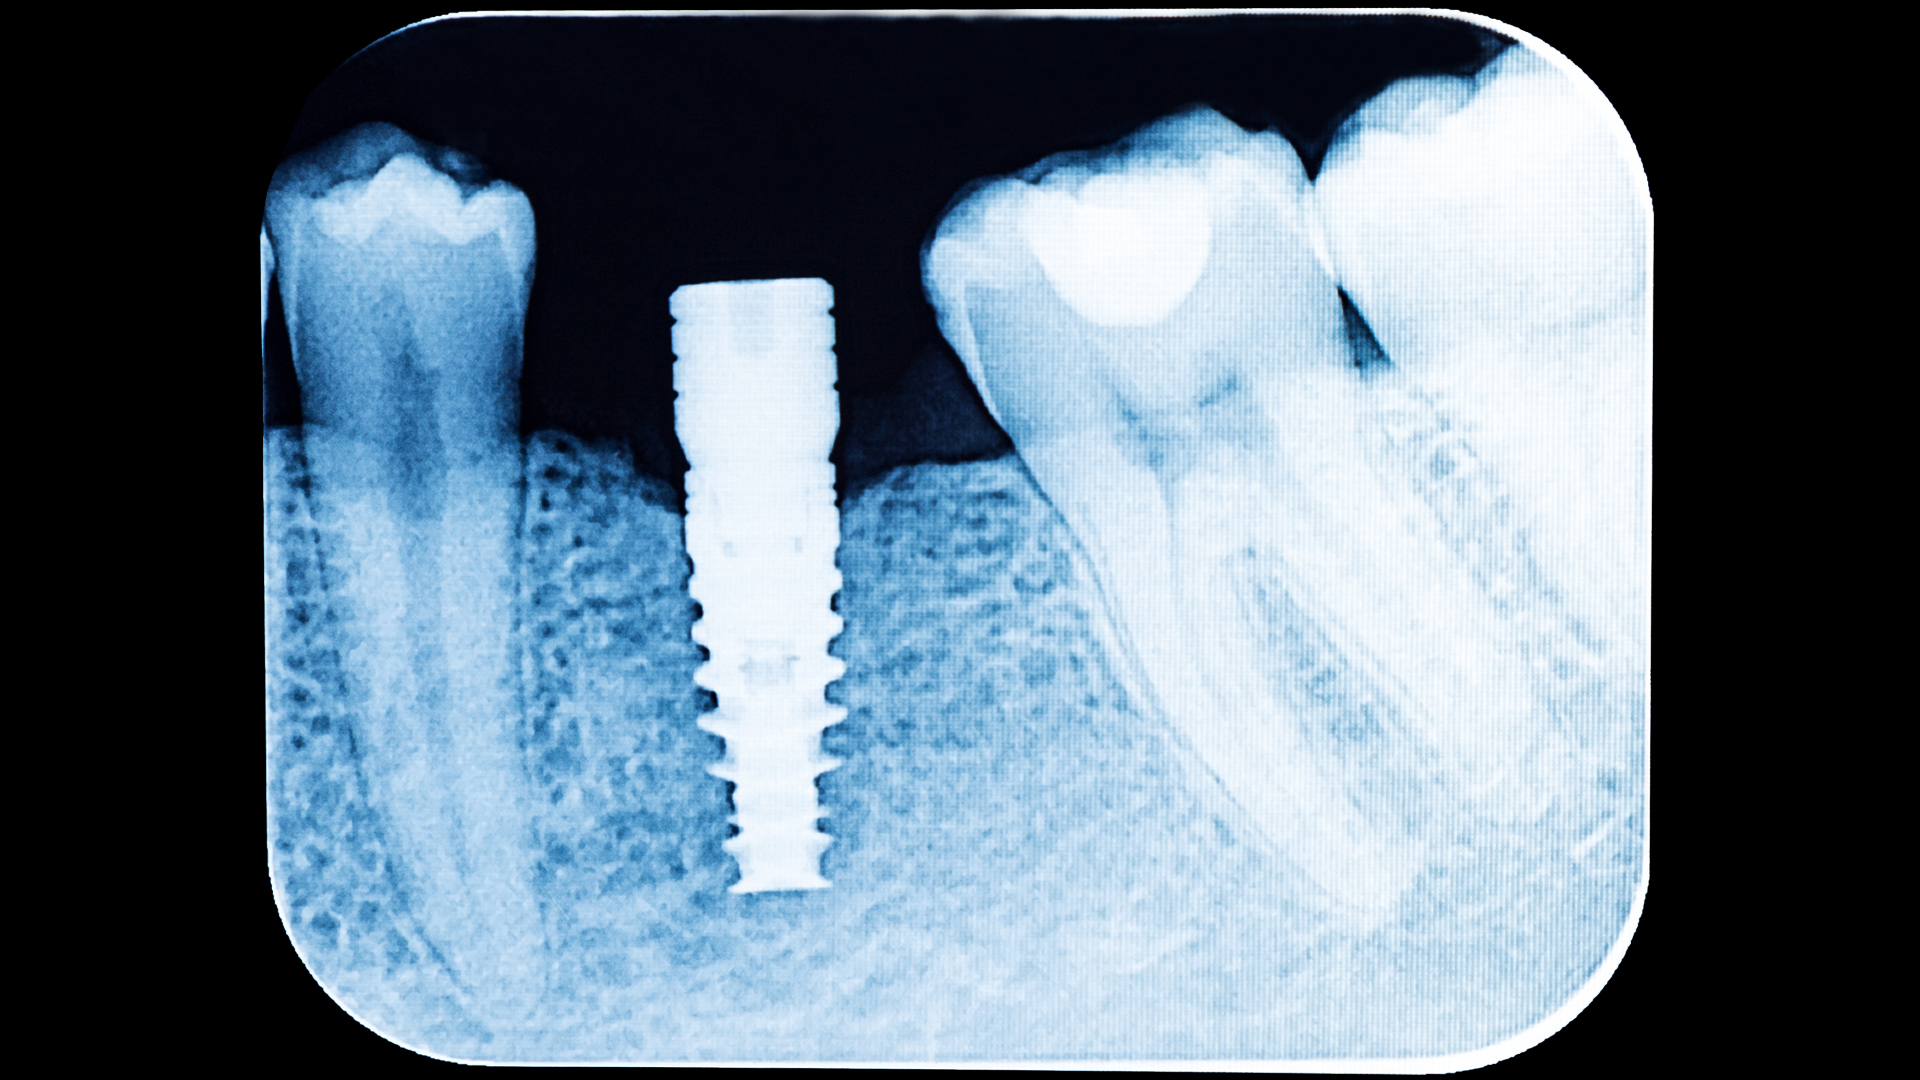

Figure 1

clinical example of peri-implant mucositis (courtesy of Dr. Liran Levin)